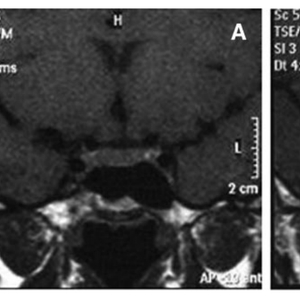

辅助检查:外院血常规、粪常规未见异常,肝肾功能、血糖正常,性激素全套血泌乳素147ng/ml (正常范围2.5-15ng/ml;免疫荧光法),余正常。腹部超声示轻度脂肪肝,子宫附件超声未见异常。垂体MRI平扫/增强未见异常(图1)